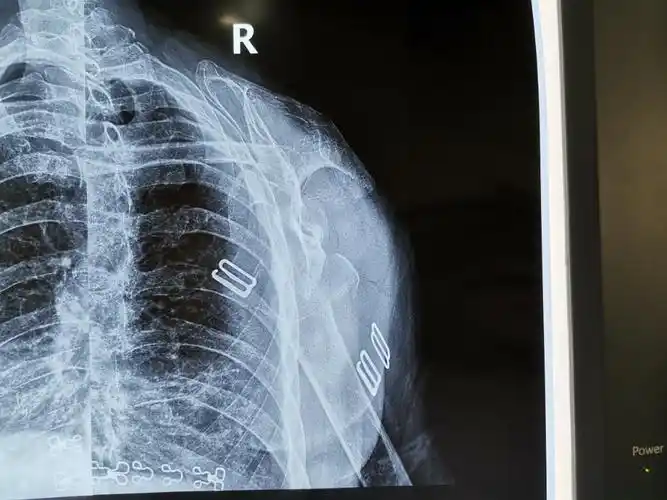

请问一下肩胛骨正侧位怎么摆位和影像显示谢谢

肩关节的x线照片或x线照片.另外一个视图名是冈上出口

右肩关节斜位片